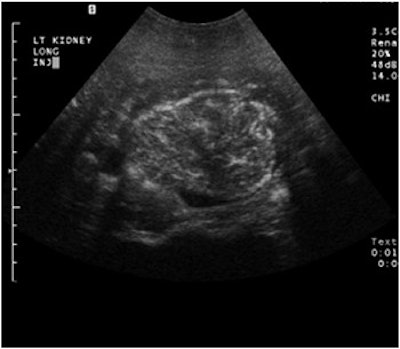

![]() |

A complex cystic mass with a solid portion slightly higher in echogenicity in the cystic component, pre-contrast (above) and post-contrast administration (below). The echogenic component is markedly enhanced on contrast and is a cystic renal carcinoma. Images courtesy of Dr. Richard Barr, Ph.D.